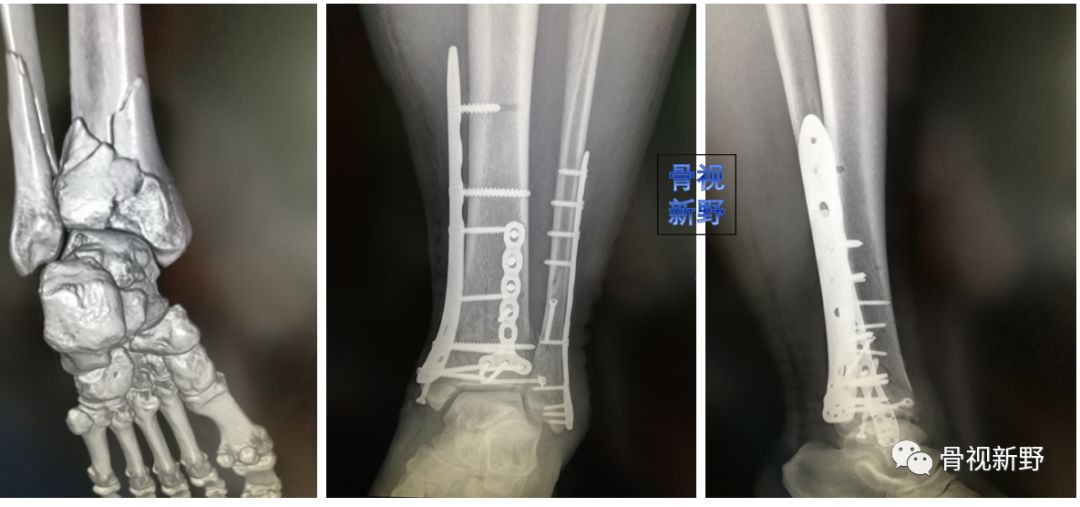

内踝垂直型骨折的buttress固定

内踝骨折根据骨折线走形方向可分为:横形、斜形、粉碎、垂直骨折,其中斜形、垂直形,特别是垂直型骨折的剪力较大,常规克氏针、空心钉、张力带等固定措施不能很好中和剪切力,应用buttress钢板的防滑原理可减少不愈合及畸形愈的并发症。

内踝斜形骨折—腓骨远端锁定钢板防滑固定(J Foot Ankle Surg. 2015 ;54(6):1202-5.)

腓骨远端锁定板防滑+克氏针防旋固定

锁定重建板单皮质固定防滑+空心钉加压固定